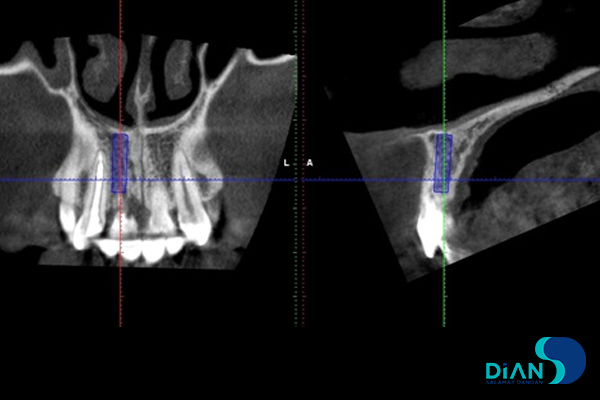

In this situation, there are no options for tooth restoration in terms of unreliable result. So the patient rejected such tactics. It was decided to do immediate implantation after tooth extraction. The dentist made treatment plan and implants position according to the size of CBCT results.

In addition he chooses Bio3 Progressive active implant 3.8/13 according to the D2-D3 bone type in order to achieve a sufficient primary stability for successful osseointegration.